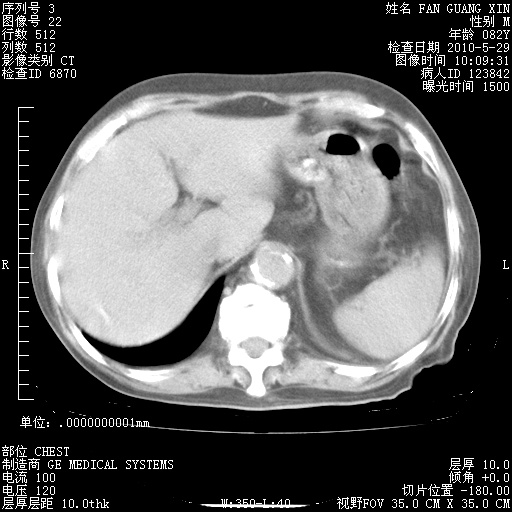

再治疗10天后的肺部CT

再治疗10天后的肺部CT 纵膈窗

阅读此次胸部CT,肺间质渗出性改变较入院时有吸收。目前从体温、白细胞、中性分叶明显增高,肯定存在细菌感染(发生医院感染哦,若无消化道及泌尿系统等感染的依据,肺部感染可能大)。若你院头孢哌酮舒巴坦钠耐药率较高,同意你的方案,若48小时体温仍高,可考虑使用碳青霉稀类抗菌药物,同时可予超声雾化、注意滴数时加大液体量。白蛋白33.30g/L较低哦,需加强营养等支持治疗。